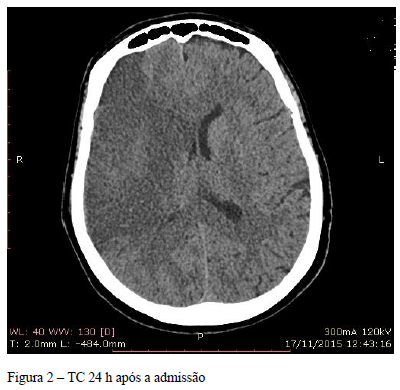

No segundo dia de internação, está sonolenta, mas sem outras alterações evolutivas no exame

neurológico. Glicemia capilar 180 mg%. TC de crânio 24 h após a admissão corresponde à

FIGURA 2.